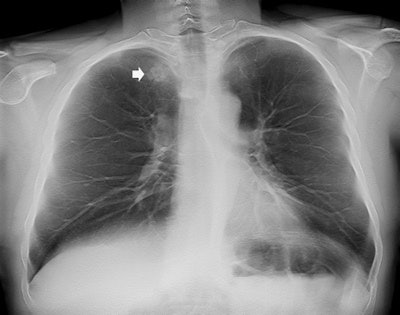

Compared with CXR, digital tomosynthesis produces superior images for identifying the intra- or extrapulmonary lesions previously suspected based on initial CXR interpretation. It also removes overlying anatomical structures, enhances local tissue separation, and provides more depth of information of the structure of interest. And it has a lower radiation dose than CT.

The study results suggest that digital tomosynthesis may confirm or rule out pulmonary lesions and pseudolesions and also differentiate true pulmonary opacities from those due to pleural or thoracic wall lesions with a clear improvement in diagnostic accuracy, confidence, and interreader agreement in comparison with CXR and with a modest increase in the radiation dose and interpretation time, the authors wrote.

Compared with CT, the main limitation of digital tomosynthesis is the limited depth resolution caused by the limited tomographic sweep angle. In this study, all findings misinterpreted at digital tomosynthesis were subpleural or located in the region of the lung in the proximity of the chest wall, where the limited depth resolution of digital tomosynthesis may hamper the correct spatial location of the findings.